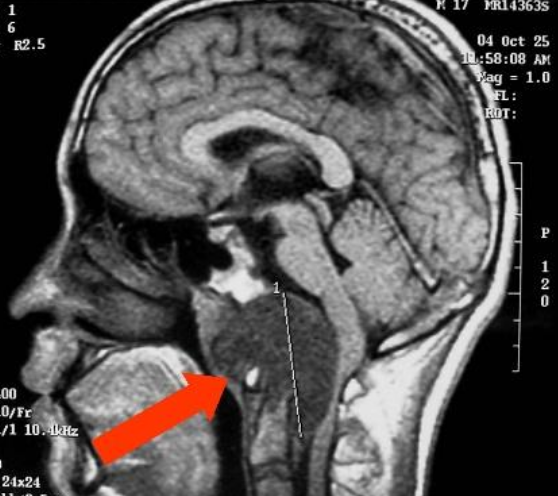

一名37岁的妇女因颈部疼痛和下颅神经功能障碍(声音嘶哑和吞咽困难)被咨询至我科。她先前被诊断出患有(CCJ) 颅颈交界处脊索瘤 ,并且先前在另一家医院进行了两次手术切除尝试...

法国一位37岁的女士因头痛、视力下降严重,到医院检查,被诊断出颅颈交界处(CCJ) 脊索瘤 。随后在一家比较医院治疗,该院采取了乙状窦后入路手术切除,但不久后,便再次复...